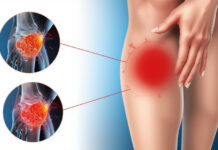

Your knees will have a tiny quantity of fluid when they are healthy. Your knee joint will move more easily and painlessly thanks to the lubricating properties of that fluid. However, extra fluid can occasionally build up in and around your knee joint. In addition to feeling painful, your knee may appear bigger, puffier, or swollen.

Knee effusion, or water on the knee, is a common term used to describe knee swelling. An illness, an injury, or prolonged joint use could bring it on. Regardless of the source, knee joint swelling is abnormal and can reduce knee function and flexibility. Additionally, it may cause pain and make it difficult to stand and move normally.

Your body’s natural defense mechanisms are what cause water to accumulate on your knee.

When you injure your knee joint, your body produces more joint fluid to cushion and lubricate it, which can cause discomfort and inflammation.

The excess fluid results in:

Swelling: You may notice a noticeable increase in the skin surrounding your kneecap, especially when comparing the affected knee to the other one.